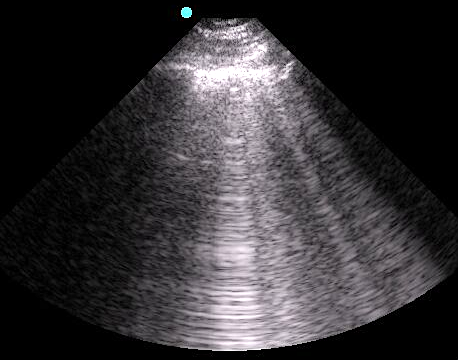

- Figure 5. B-lines

- Vertical hyperechoic comet-tail reverberation artifacts that arise from the pleural line, erase A-lines, move with respiration, and extend to the bottom of the sonographic window without fading.

- Occur due to multiple reflections of sound waves trapped between air and water-rich structures of pulmonary interstitium

- 1-2 B-lines may be detected in dependent regions of normal aerated lung.19

- < 3 B-lines within an intercostal space is considered normal.18, 19

- With increasing density or fluid, more B-lines will appear and coalesce into “lung rockets.”)